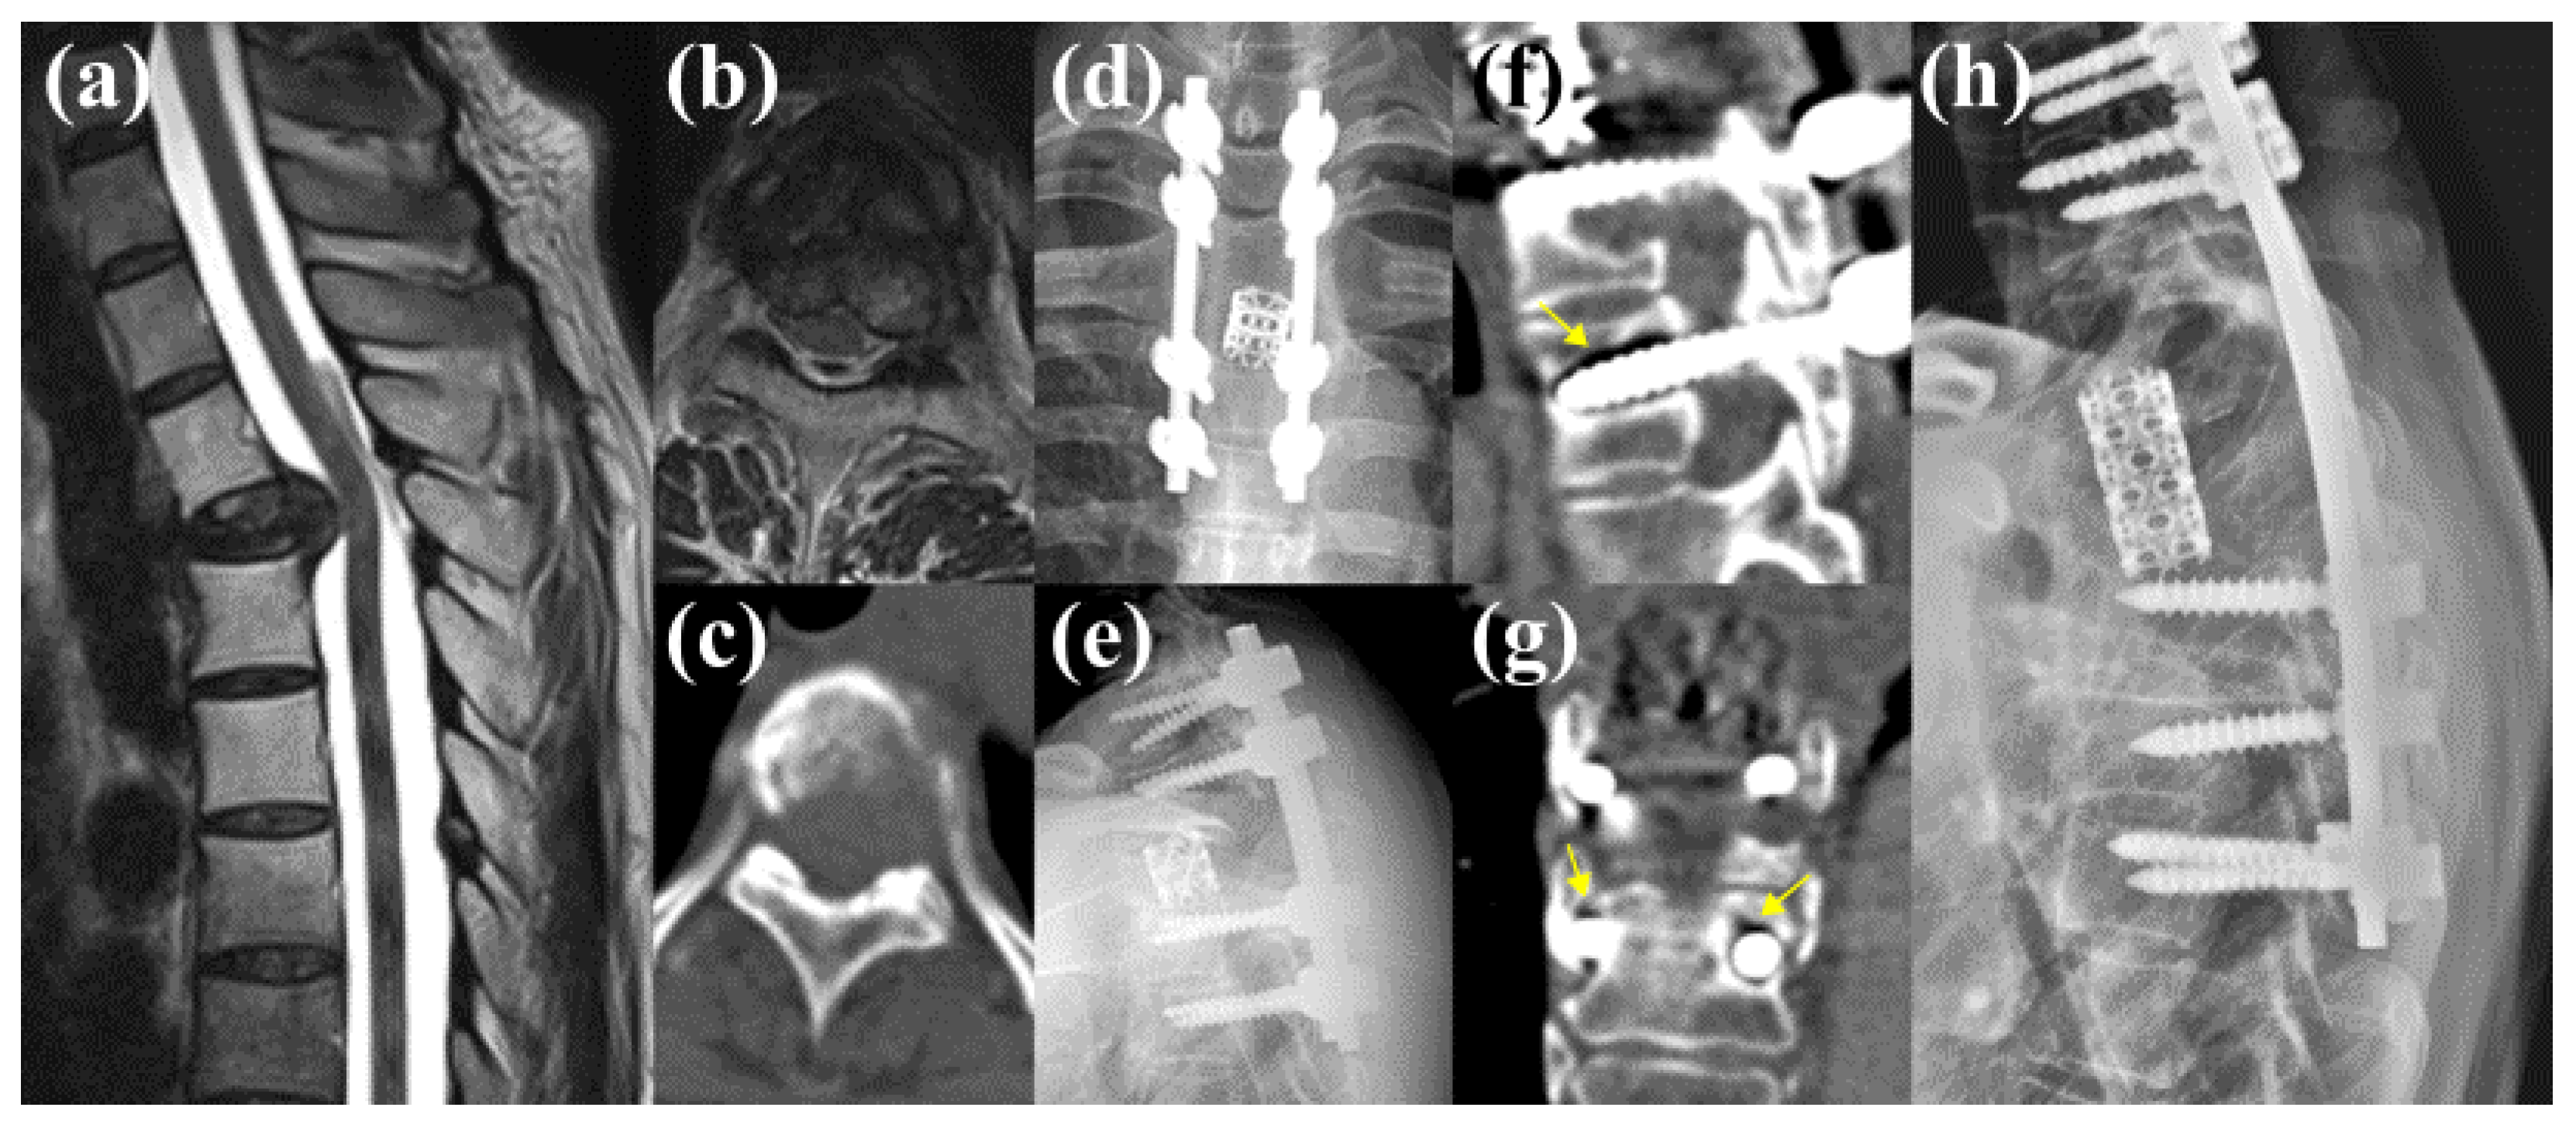

3.5.2. Case 2